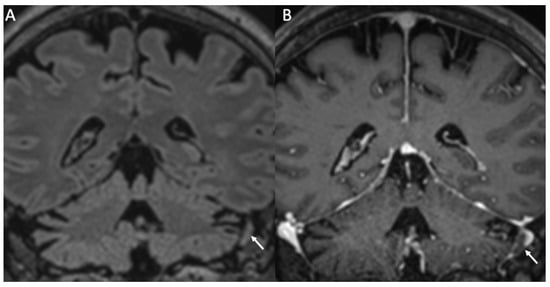

| Varicella Zoster Virus | • Leptomeningeal enhancement • Cerebellitis |

| Cytomegalovirus | • Hyperintense areas in T2 and FLAIR in the periventricular white matter • Ventriculitis |